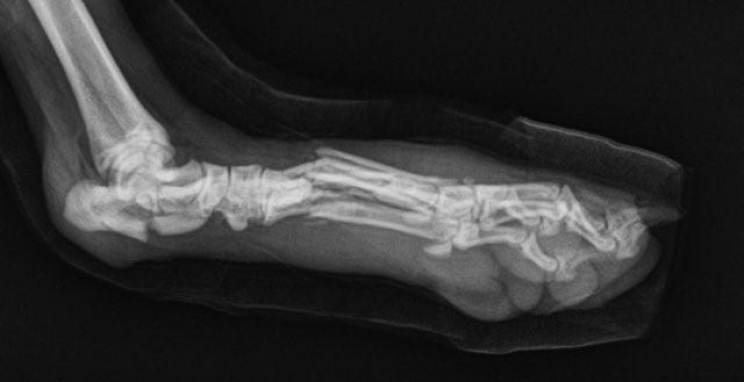

Definire una frattura non è difficile: è la rottura di un osso. Tutte le ossa possono fratturarsi, ma quelle che lo fanno più frequentemente sono quelle degli arti, le ossa lunghe, quindi quelle che compongono le zampe (omero, radio, ulna, femore e tibia).

Fondamentalmente, il nostro compito di proprietari è quello di impedire che la situazione peggiori. Solo una radiografia, una lastra, fatta dai veterinari potrà far capire quale sia effettivamente il problema e se ci sia bisogno di un intervento chirurgico per risolvere la situazione.